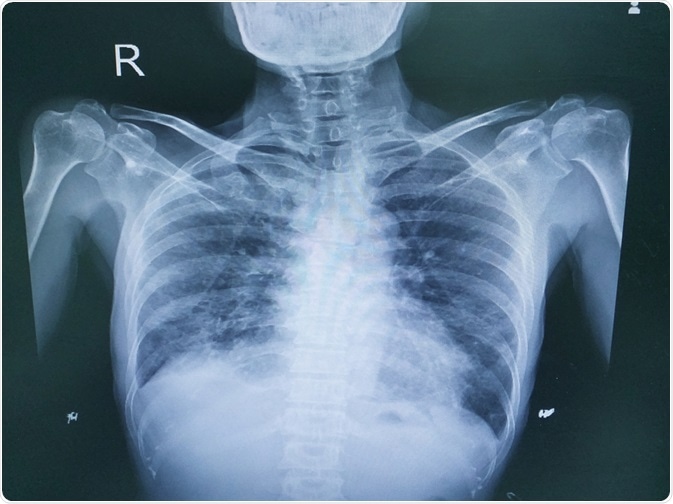

Image Credit: April stock / Shutterstock.com

Image Credit: April stock / Shutterstock.com